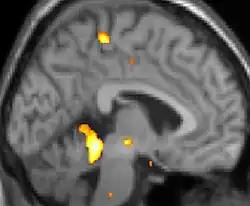

![]() |

| Tomografia PET mostrando áreas ativadas na dor. | ||

| VBM mostrando diferenças estruturais entre cérebros | ||

As reais causas da cefaleia em salvas (CES) ainda são desconhecidas, mas, de acordo com alguns estudos, os padrões das crises, as influências pelo horário do dia e as estações sugerem que o relógio biológico do corpo está envolvido. Nos seres humanos, o relógio biológico está situado no hipotálamo. Durante um ataque, o hipotálamo libera substâncias químicas que podem estimular as células nervosas no cérebro, causando dor e outros sintomas. A hiperatividade nervosa também pode causar um alargamento (vasodilatação) das artérias no lado afetado do cérebro. Uma teoria é que as dores são causadas por um alargamento dos vasos sanguíneos, que pressionam sobre os tecidos nervosos próximos, causando dor.[5] Exames de ressonância magnética sugerem dilatação da artéria oftálmica durante uma crise de cefaleia, enquanto a tomografia por emissão de pósitrons (PET) revela atividade dentro do seio cavernoso. Em alguns casos, existem fatores genéticos também, pois é mais comum entre familiares.[6]